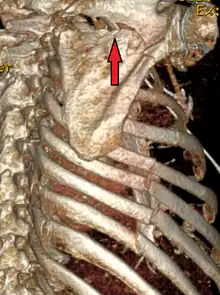

| A right sided scapula fracture with rib fractures underneath seen on a 3D reconstruction of a CT scan | |